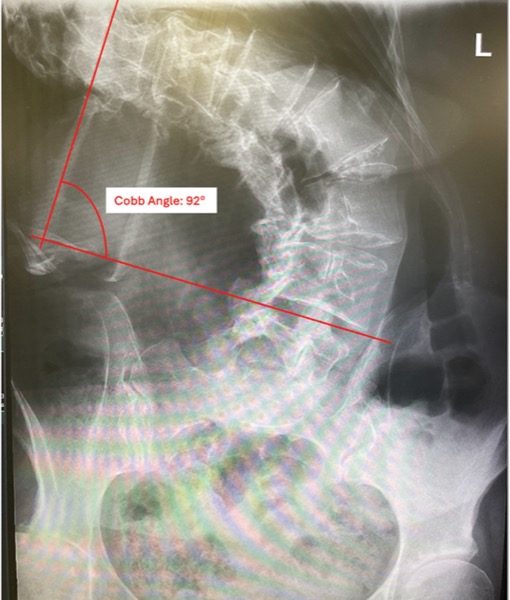

For patients with severe scoliosis, careful preoperative planning is paramount for intraoperative and postoperative care